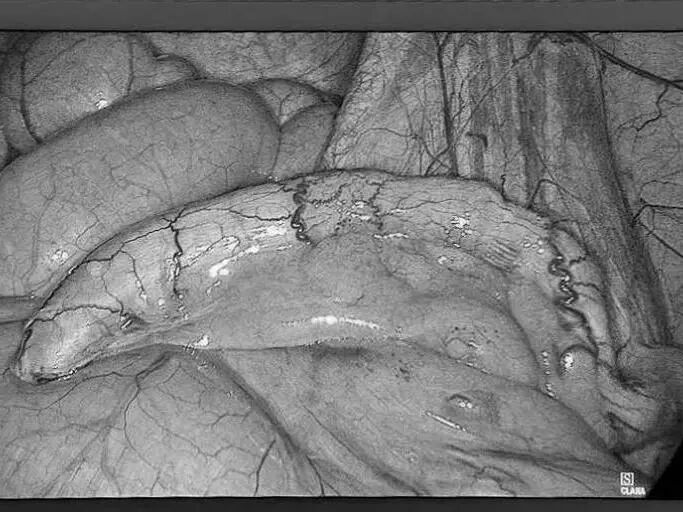

您是否正在经历 肛周肿痛、瘙痒的困扰? 是否发现过便血 或是有小肉球脱出来? 是不是因为觉得尴尬 所以一直拖着没去看? …… 这些难言之隐的背后 往往是痔疮、肛裂等 肛周疾病的信号 这些常见问题,往往与我们的日常生活习惯息息相关:长时间坐着不动、如厕时久蹲、饮食中缺乏蔬菜水果都可能增加患病风险。预防的关键在于主动调整: ✔饮食要“润”:多吃蔬菜、水果、粗粮,保证饮水,让大便保持通畅松软。 ✔久坐要“动”:每隔一小时起身活动几分钟,减轻肛周压力。 ✔如厕要“快”:减少如厕时间,避免久蹲和过度用力。 ✔清洁要“轻”:便后保持清洁,用温水冲洗或柔软纸巾轻拭。 养成良好的生活习惯,是守护肛周健康的第一道防线。 目前,治疗这类疾病的方法有很多。在贵州航天医院普外科,我们在常规诊疗基础上,进一步融入了中医调理的优势,为您提供一种更注重恢复过程中的舒适度、也更关注身体的整体调理特色方案——中西医结合治疗肛周疾病,希望能帮助您更安心、更顺畅地解决难言之隐。 【中西医结合,优势互补】 ※西医精准明确,技术微创:借助电子肛肠镜等设备清晰诊断,并运用PPH(吻合器痔上黏膜环切术)、TST(选择性痔上黏膜吻合术)等微创手术技术,精准处理病灶,创伤小、出血少。 ※中医整体调理,促进康复:通过内服外用中药,协助术后消肿止痛、促进创面愈合,并帮助调整内在体质,减少复发。 【中西医结合诊疗的优势】 ▶术前可中医干预:对处于急性炎症期的患者,先行中药坐浴、外敷等缓解肿痛,创造更好手术条件,部分患者可能因此免于手术。 ▶术中微创精准:由经验丰富的肛肠外科医生操作,注重保护正常功能组织。 ▶术后康复加速: •中药内服调理:根据个人体质开具药方,促进恢复。 •中药坐浴外治:使用科室配置的洗剂,帮助保持清洁、缓解疼痛、舒适伤口。 •专业西医护理:配合规范的伤口换药与护理,保障愈合过程顺利。 •多模式镇痛:采用中西药结合的多种镇痛方式(如口服、外用、中药制剂等),有效缓解术后疼痛,帮助您更舒适、安心地度过恢复期。 适合以下常见肛周疾病患者: 各期痔疮(内痔、外痔、混合痔)、肛裂、肛周脓肿、肛瘘、直肠息肉、肛周湿疹、肛门尖锐湿疣、肛乳头瘤、肛门狭窄、肛门失禁等。 温馨提示: 1.肛周疾病重在早发现、早干预,请不要因羞涩而延误最佳治疗时机。 2.本文仅为疾病科普与诊疗介绍,不能替代任何专业的医疗建议,如有任何健康问题,请务必及时咨询并遵从专业医生的诊疗意见。 注:部分图片来源于网络,如有侵权,请联系删除。 贵州航天医院普外科专家简介 高大勇 普外科(肛肠外科)学科带头人、名誉主任,主任医师、教授 临床擅长:对中西医结合诊治肛肠学科各种常见病、多发病及疑难杂症等具有丰富的临床经验。 原遵义市第一人民医院(遵义医科大学第三附属医院)、遵义市中医院肛肠科主任。中华中医药学会肛肠分会常委,全国中医肛肠学科名专家,中国健康促进与教育协会肛肠分会常委,中国康复医学会肛肠疾病康复专业委员会常委,中国民间中医医药研究开发协会肛肠分会副秘书长,中国医师协会中西医结合肛肠医师专业委员会常委,国家二级心理咨询师,贵州省第一批中医名医工作指导老师,遵义市名中医,遵义市肛肠学会会长,遵义市肛肠质控中心名誉主任,遵义市中西医结合学会名誉会长,遵义市健康科普专家,原贵州省中西医结合学会肛肠分会副主任委员、贵州省中医肛肠质控中心副主任、遵义市医学会医疗鉴定委员会专家、遵义市卫生系列高评委。发表论文30余篇,主编和参编医学著作5本,主持省级科研课题2项、市级科研课题2项、院级科研课题1项。 梁 跃 普外科党支部书记、主任,主任医师 临床擅长:对普外科各类肿瘤手术具有丰富的临床经验。 毕业于遵义医学院,遵义市医学会小儿外科学分会常务委员,遵义市肛肠协会理事,遵义市医学会核医学分会(第二届)委员会委员;荣获第三期“黔医人才计划”优秀学员称号;主持市级课题1项,完成省级课题1项,在国内各类刊物上发表论文10余篇。 钱科洪 民盟盟员,普外科副主任医师 临床擅长:从事普外科临床工作30余年,对各类普外科疾病的诊治、乳腺、甲状腺、胃十二指肠、结直肠等疾病及疑难杂症具有丰富的临床经验。 毕业于遵义医学院临床医疗系,2009年前往中山大学附属第一医院微创外科进修学习,在国内各专业期刊发表论文数篇。 贵州航天医院普外科简介 基本情况 贵州航天医院普外科成立于1968年,前身属于航天部O61基地3417医院外一科,1998年3417医院、3427医院合并后更名为普外科,下设胃肠外科、肛肠外科2个亚专业科室,拥有在全市较为先进的专科设备和技术,是中国疝病专科联盟单位,贵州医科大学附属医院胃肠外科专科联盟单位。开放床位40张,配备医护人员21人。 专科特色 普外科致力于胃肠及肛肠疾病的外科临床诊治及科研,以腹腔镜微创外科技术为本,形成以快速康复治疗胃肿瘤、结直肠肿瘤、小肠肿瘤、直肠脱垂、肥胖病、急腹症、各类疝、痔、瘘等专科特色,同时注重胃肠疾病尤其是结直肠恶性肿瘤的基础研究和临床转化研究,总体诊断和治疗水平在区域同级医院居于领先水平。 开展手术:腹腔镜下胃癌根治术,腹腔镜下袖状胃切除术,腹腔镜下胃肠道间质瘤切除术,腹腔镜下结、直肠癌根治术,胃癌、结直肠癌的精准治疗,腹腔镜下小儿疝气、成人疝修补术,腹腔镜下阑尾手术,内痔的硬化注射治疗及痔疮的微创治疗:ATH、PPH、TST,直肠脱垂的各种手术治疗,难治性伤口VSD技术,鼻胃肠管、肠梗阻导管置入术,肛肠术后间歇性导尿技术,并引进了中医适宜技术,也为各种化疗患者提供输液港安装,提高患者就医体验。 腹腔镜下腹股沟疝 无张力修补术 腹股沟疝里金斯坦 (Lichtenstein)手术 PPH微创术治疗环状混合痔 黏连性或炎性肠梗阻-肠梗阻导管 腹腔镜袖状胃切除 腹腔镜阑尾切除术 腹腔镜阑尾肿瘤切除术 腹腔镜下结肠癌根治术 诊疗范围 胃肿瘤、结直肠肿瘤、小肠肿瘤、肥胖症、各类急腹症、腹部外伤、腹壁疝、便秘、直肠脱垂、痔疮、肛瘘、肛裂等胃肠、肛肠外科疾病。 END